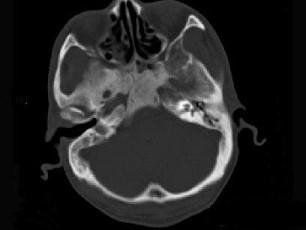

问题 男性,56岁,鼻咽癌放疗后复查,CT扫描如图所示,请选择正确的答案 ( )

选项 A、放疗后骨炎 B、骨瘤 C、骨结核 D、致密性骨炎 E、化脓性骨髓炎

答案 A